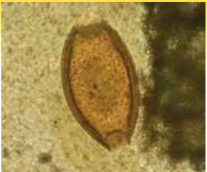

Trichuris trichiura